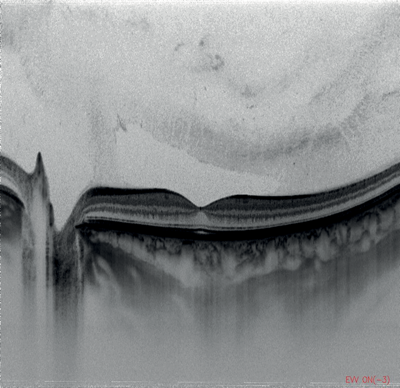

Figures 1-4: Swept-source OCT (DRI OCT-1 Triton, Topcon) images of healthy eyes that clearly delineate features in the vitreous, including area of Martegiani, bursa premacularis and posterior hyaloid, right through to the sclera, in the same single scan.

Topcon’s newly-introduced swept-source DRI OCT Triton can capture 256 B-scans in less than three seconds, with high speed scanning of 100,000 A-scans per second and a 1050nm wavelength which can penetrate easily through cataracts and haemorrhages. It features widefield 12 by 9mm scan screens for both glaucoma and macular pathology in one scan, with consistent signal strength from cortical vitreous to the sclera with an average of up to 128 times, automatic detection of seven retinal layers, as well as 2.6 micron digital resolution. The DRI OCT Triton has a built-in high resolution colour fundus camera, fundus guided acquisition (SmarTrack) and the option of an anterior imaging module. The Triton Plus also features fundus autofluorescence and fluorescein angiography, and an OCT angiography module is currently under development.